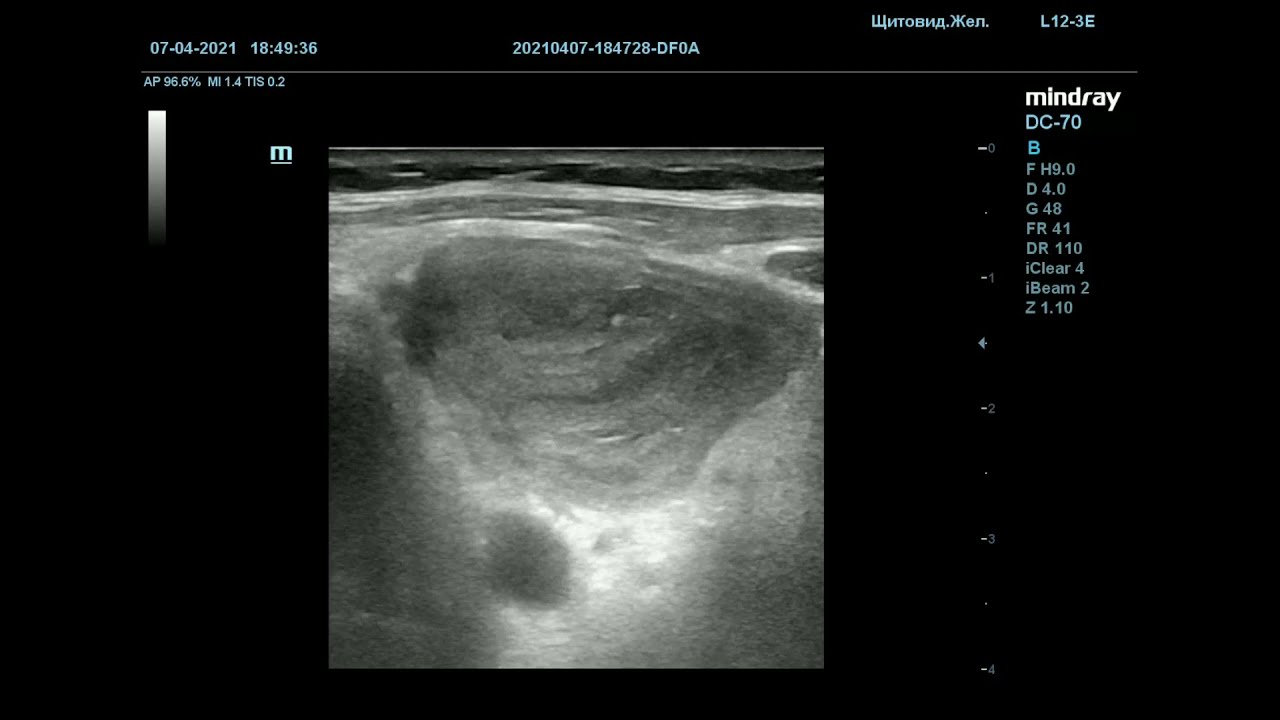

• Дуплексное сканирование сосудов, предоставляющее информацию о размере тромба, степени окклюзии, состоянии стенок сосудов и нарушении кровотока.

Окклюзивный тромбоз ВЯВОкклюзивный тромбоз ВЯВ